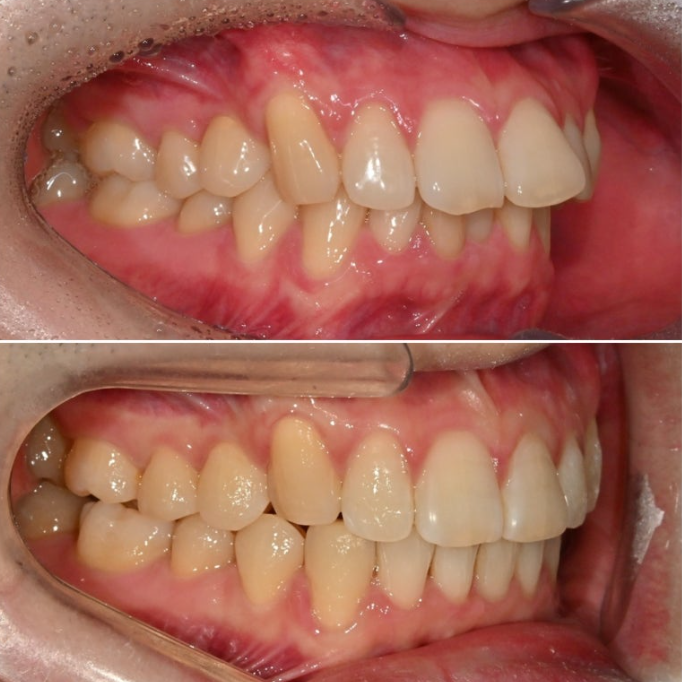

25.02

올해 초, 교정치료를 위해 내원한 30대 후반의 환자분입니다.

앞니가 깊게 물리는 과개교합.

중심선 불일치. 정도가 보입니다.

앞니가 많이 뻗쳐있습니다.

위 앞니 뻗침이 심하면 위 아래 앞니 사이 간극이 커지죠.

위아래 어금니 물리는 교합관계는 그래도 1급에 가깝습니다.

악궁모양이 약간 찌그러진 형태입니다.

25.06

25년 2월부터 6월까지 14개 첫세트 장치를 모두 낀 후 모습입니다.

과개교합은 대부분 개선되었고 중심선 불일치도 개선되었습니다.

일부 배열상 미진한 부분을 추가로 개선하기 위해 추가장치 제작에 들어갔고 25년 12월 드디어 치료를 마무리 했습니다.

25.12

중심선은 맞아졌으며

어금니 교합은 1급 교합관계를 보입니다.

앞니 뻗침은 좋아졌네요.

이제 전후 비교 보겠습니다.

25.02~25.12

과개교합의 개선으로 아래앞니가 온전히 보이게 되었습니다.